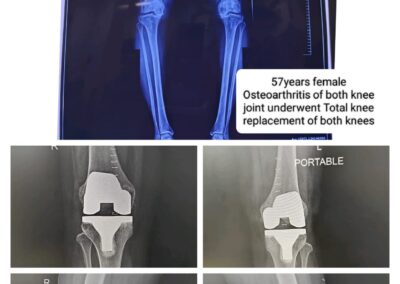

Case study